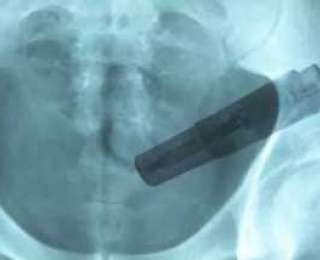

Доктор расспросил мужчину о перенесенных в недавнем прошлом заболеваниях и рационе питания, а затем отправил на рентгенологическое обследование кишечника. Страдалец попробовал возражать против рентгена, но, узнав о том, что без снимка медики не смогут назначить правильное лечение, дал свое согласие на проведение процедуры.

Изображение на снимке заставило врача и ассистирующего ему Стиви Попа недоуменно переглянуться: в толстой кишке был явно виден инородный предмет с кнопками.

“Мы рассмотрели в кишечнике большой объект и сразу поняли - это вибратор, - вспоминает санитар. - Я впервые стал свидетелем обнаружения в человеке работающей секс-игрушки”.